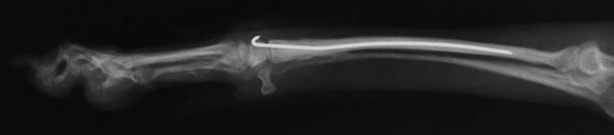

前肢の骨折:橈骨尺骨骨折

骨折時

手術後

骨折治癒

最後に金属の

金具を取り除き

完治